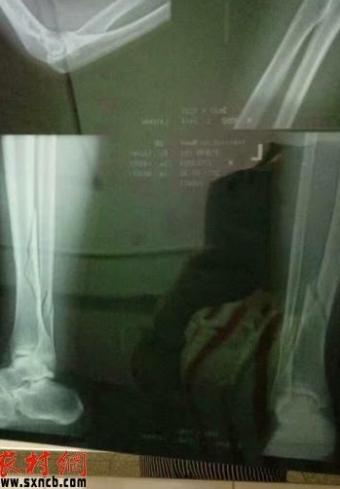

陕西农村网—陕西农村报讯(乔东斌 记者 王军)临近高三学生离校,因为“撕书”原因,富平县迤山中学一高三男生与学校巡查的教师发生矛盾,目前,该生因左腿骨折原因正在住院治疗。提及当日事发情况,该生坚称是老师持棍暴打造成,强调被打期间,曾向老师回话讨